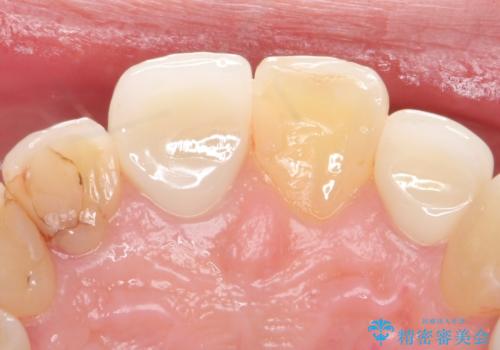

- 継ぎ接ぎになった前歯を綺麗にしたいとのことで来院されました。

継ぎ目のないクラウンで修復処置していきます。

- 左上2 仮歯+ジルコニアクラウン:11,000円+121,000円費用は治療当時の料金となります

精度の良い被せ物を装着することで、違和感のない自然な見た目を獲得することができます。